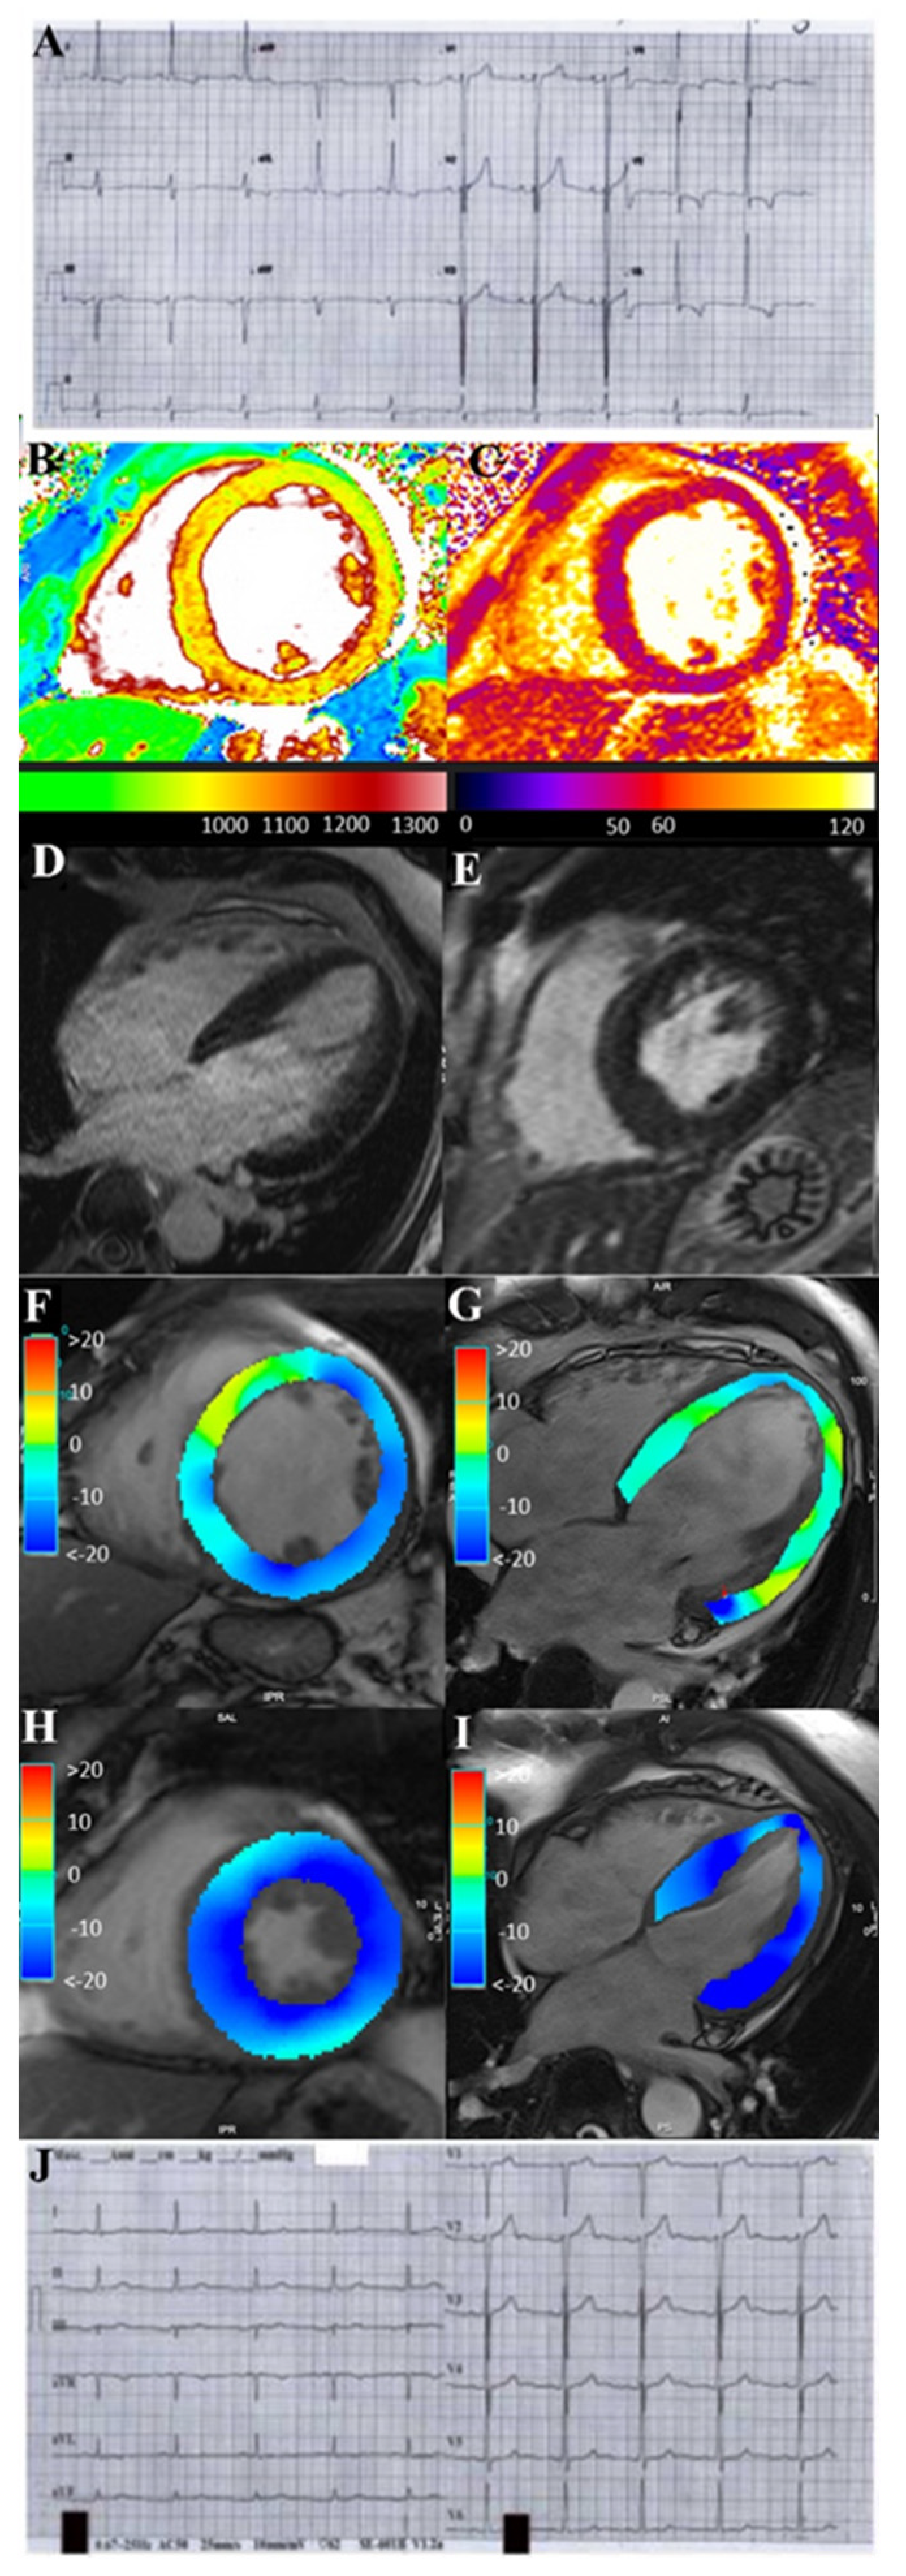

All five patients presented moderate/severe skin involvement. Two patients had also arthritis and one patient eye disease (dry eye). Baseline NYHA Class was III/IV. Electrocardiogram documented premature ventricular contractions, supraventricular tachycardia and non-sustained ventricular tachycardia in 3 patients, atrial fibrillation in 1 patient and ST segment/T wave abnormalities in 1 patient (Figure 1 panel A). At 2d-echo all patients exhibited left ventricular dilation (left ventricular end-diastolic diameter, LVEDD = 64.6 ± 8.01 mm) with severe reduction of ejection fraction (LVEF = 20.2 ± 5.6 %) and high filling pressure (E/E’ > 12 mmHg); moreover, right ventricular dysfunction (tricuspid annular plane systolic excursion, TAPSE < 15 mm) was present in 3 patients and pericardial effusion in 2 patients. STIR T2 weighted CMR images demonstrated hyperintensity as well as native T1 and T2 maps showed a diffuse increase of myocardial T1 and T2 values (Figure 1 panels B, C) due to diffuse edema. CMR (Figure 1 panels D, E and video) confirmed the hypokinetic dilated cardiomyopathy. Late gadolinium enhanced images did not show any fibrotic area (Figure 1 panels F, G) except in 2 patients.

At 6-month-follow-up (Table 2), 3 patients treated with prednisone and azathioprine improved with NYHA Class reduction from III to II and LVEF increased from 22.6% to 48.6% while 2 patients on SK recovered completely with reduction of NYHA Class from III/IV to I, LVEED decreasing from 66 to 53 mm and normalization of LVEF from 16% to 55% (Figure 1 panels H, I and video 1). Arrhythmias and ST segment/T wave abnormalities (Figure 1 panel J) on electrocardiogram disappeared. CMR showed resolution of edema on STIR T2 weighted image and reduction of native T1 and T2 values on mapping sequences. Patients 1 and 5 exhibited persistence of late gadolinium enhancement as a consequence of myocardial fibrosis. Skin lesions almost completely disappeared (Figure 2 panel B) while arthritis improved and dry eye healed.

Figure 1. ECG (panel A and J) and CMR (panel B-I) findings of pt 5 with severe PS-related myocarditis at baseline and following 6 months SK administration.

ECG shows complete normalization of ST-T abnormalities after therapy (panel A: ecg before therapy, panel J ecg post therapy).

CMR: Native T1 (B) and T2 (C) maps show a diffuse increase of myocardial T1 and T2 values due to diffuse edema during acute phase (B-C). CineMR images, acquired on mid ventricular short axis (D) and four chamber (E) views at end systolic phase show a marked reduction in LV function, respectively visualized as impairment of GLS and GCS strain values. Late gadolinium enhanced images (F-G) do not show any fibrotic or necrotic myocardial areas. CineMR images at follow-up (H-I) show a complete recovery of LV function with normal GCS and GLS strain values. LV: left ventricle; GCS: Global Circumferential Strain; GLS: Global Longitudinal Strain.